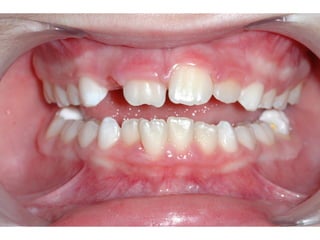

Πρώτη σχολική ηλικία 6-10 ετών

   Αρχίζει αλλαγή των τομέων και η ανατολή των

πρώτων μόνιμων γομφίων (μεικτή οδοντοφυΐα)

   Παρατηρούμε η αλλαγή δοντιών να γίνεται με τη

σωστή σειρά και στη σωστή θέση

   Μπορεί να χρειαστεί πρώιμη ορθοδοντική

θεραπεία, για να αποφευχθούν πιο δύσκολες και

πολύπλοκες εργασίες αργότερα

   Διατήρηση νεογιλών δοντιών στον οδοντικό

φραγμό μέχρι τη φυσιολογική τους απόπτωση